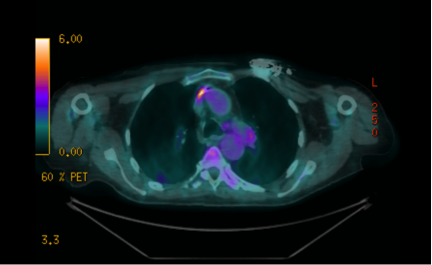

Poster abstracts – FPM Centenary Conference – 7th December 2018

16 1a

432 × 265 pixels